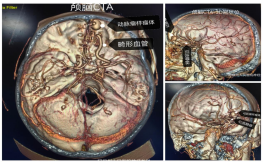

5月22日,阿坝州人民医院神经外科成功为一名57岁患者实施医院首例复杂颅脑硬脑膜动静脉瘘(DAVF)开颅夹闭手术。这场跨越高原医疗技术壁垒的“生命保卫战”,不仅填补了医院在该领域的空白,更标志着川甘青结合部复杂脑血管疾病救治能力实现重大突破。

4月18日,患者李先生因剧烈头痛被送入医院。看似普通的“酒后头晕”,却暗藏危机:CT显示颅内出血,但常规治疗却不见好转。神经外科团队通过细致问诊发现关键线索——患者长期生活在高原,伴有搏动性耳鸣和结膜充血,结合影像学检查,最终确诊为罕见的硬脑膜动静脉瘘(DAVF)。“这种病容易被误认为高原反应或普通外伤,若不及时干预可能致命。”主刀医生文家智介绍,DAVF是硬脑膜异常血管连通引发的“不定时炸弹”,手术需在毫米级血管中精准操作,稍有不慎就会引发大出血。

本区域诊断破局。团队突破高原设备限制,通过增强MRI+CTA影像与华西医院专家远程会诊,锁定隐藏在“头痛”背后的罕见病因,打破“高原头痛=缺氧/高血压”的固有认知;开颅夹闭“零误差”。在缺乏介入治疗条件的情况下,团队创新采用术中超声实时定位技术,在前颅底矢状窦旁精准夹闭瘘口,完整保留正常血管结构,实现“零并发症”治愈;多学科协作模式。神经外科联合影像科、麻醉科建立“黄金会诊链”,从接诊到确诊仅用6小时,开创高原地区复杂脑血管病多学科联动新模式。